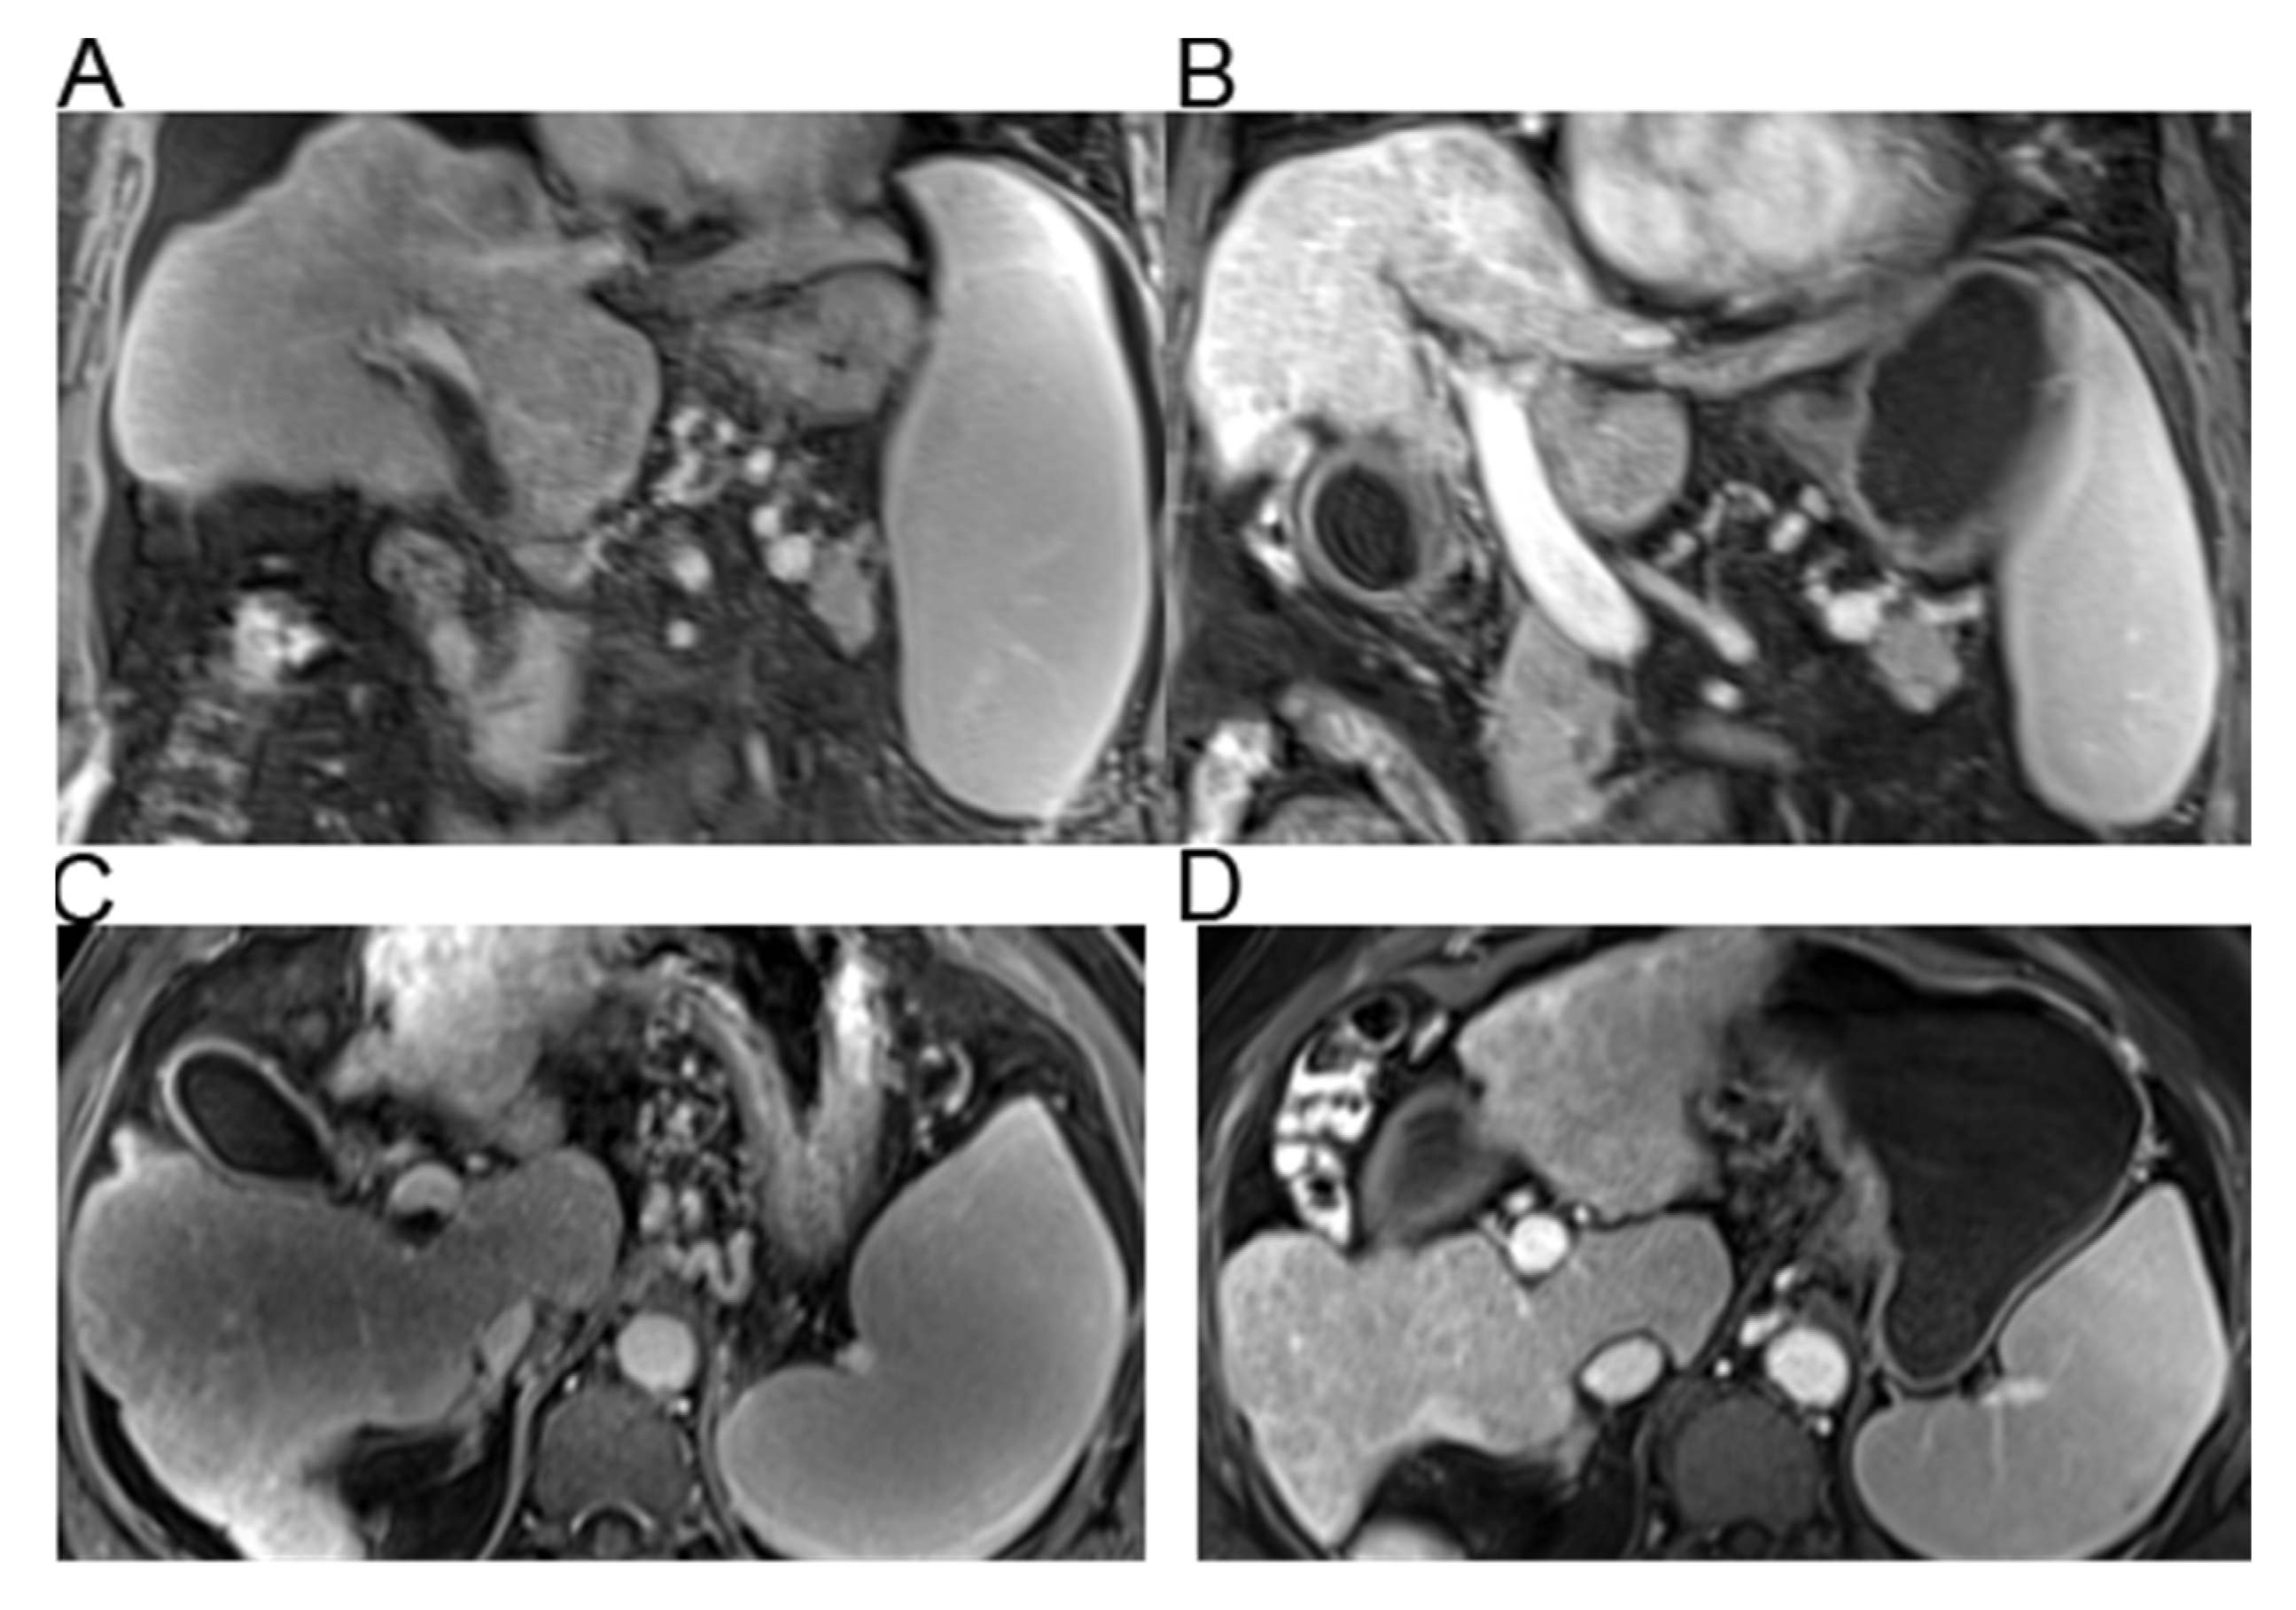

2.3. Imaging Evaluation